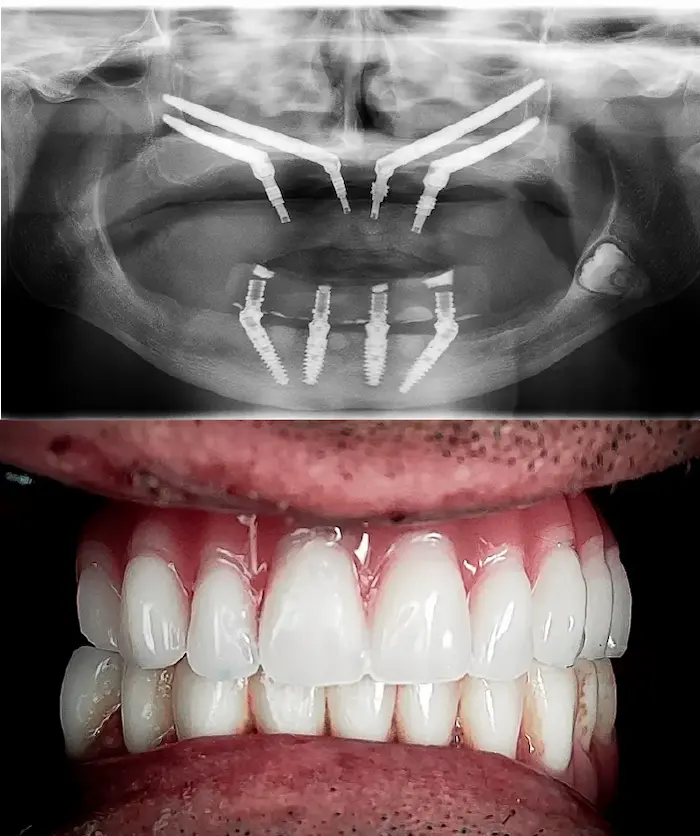

Soluzione di implantologia avanzata indicata in casi di atrofia dell’arcata superiore, quando gli impianti tradizionali o l’All-On non sono utilizzabili.

Zygoma Quad

Zygoma Hybrid

Zygoma Laterale

Gli impianti dentali zigomatici fissi sono impianti in titanio lunghi 3 – 6 cm che si ancorano all’osso zigomatico, molto più denso e stabile dell’osso mascellare. In base alle necessità il chirurgo definirà se utilizzare un impianto Zygoma Quad (due impianti zigomatici per lato), Zygoma Hybrid oppure Zygoma Laterale.